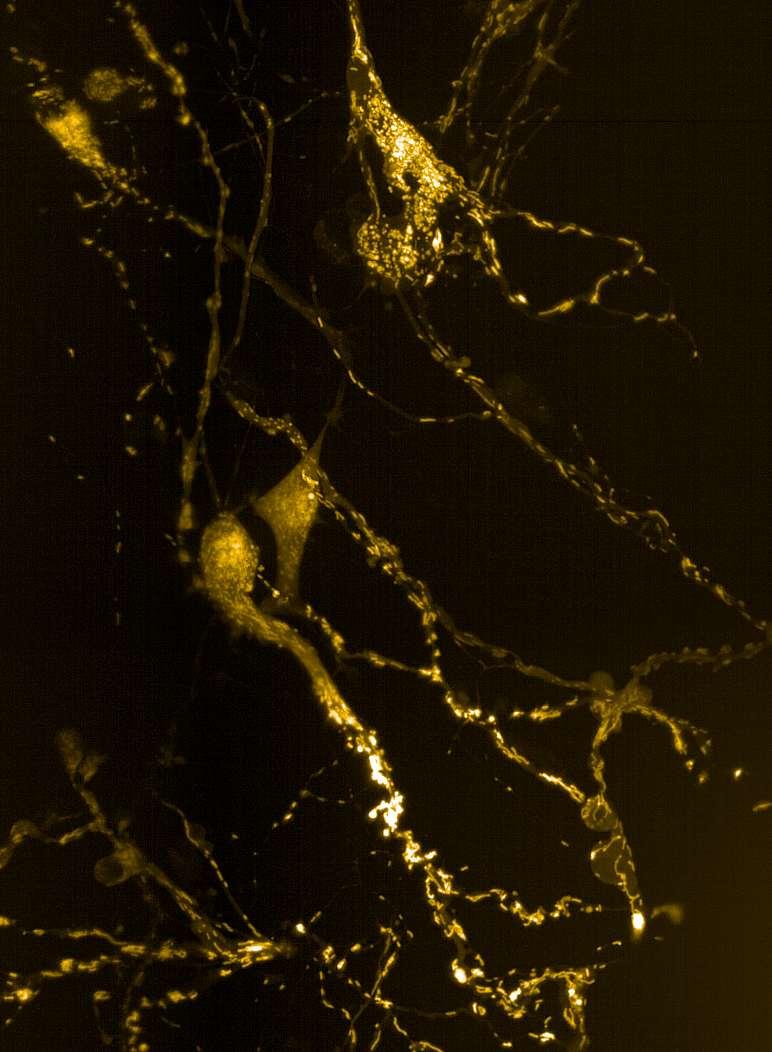

• Isogenic control and early onset Parkinson’s disease SNCA A53T mutation neurons were exposed to α-synuclein PFFs with A53T mutation

• Neurons were fixed and labelled for α-synuclein phosphorylated at serine 129 (pS129)

• PFF treated neurons show Lewy body-like perinuclear aggregates of pS129 α-synuclein